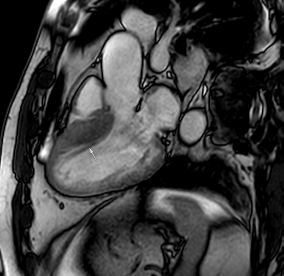

Similar to echocardiography, LV geometry can be assessed using relative wall thickness (RWT) and CMR-specific normal values for LV myocardial mass (Figure 2). LA dimensions can be assessed with Simpson’s biplane or area-length methods from the standard views, or more precisely with a volumetric assessment using an atrial short-axis stack. LA enlargement is a reliable marker of diastolic dysfunction (chronically elevated LV filling pressures) in the absence of mitral valve disease [31]. The recently introduced left atrial coupling index (LACI) is a ratio of the indexed left atrial end-diastolic volume (LAVI) in relation to the left ventricular end-diastolic volume (LVEDVI) [32]. This ratio may offer prognostic information regarding cardiovascular events such as atrial fibrillation, heart failure, and coronary artery disease-related death.

Figure 2.

Tissue characterization with Late Gadolinium Enhancement (LGE) and Extracellular Volume (ECV) Map. Adapted with permission from [33].

To avoid the low but important risks of endomyocardial biopsy, which can have an overall complication rate of up to 6% [2], myocardial fibrosis can be assessed non-invasively using CMR: LGE is suitable for detecting irreversible replacement fibrosis and myocardial scarring and T1/ECV mapping for detection of potentially reversible (reactive) interstitial and more diffuse fibrosis (not detectable by LGE) (Figure 2).

Myocytes account for approximately one-third of all cells in normal myocardium. The remaining two-thirds of cells include endothelial and vascular smooth muscle cells and fibroblasts in interstitial/perivascular spaces [2] (Figure 2). Normal CMR ECV values vary between 25.3 and 3.5% [43]. Ideally, age- and sex-corrected normal values for ECV should be used [44]. Hypertension affects both the cellular and extracellular compartments of the myocardium. In addition to cardiomyocyte hypertrophy, in HHD, fibrous tissue (primarily type I fibrillar collagen) is deposited in the extracellular matrix over time and leads to increased tissue stiffness (i.e., diastolic dysfunction) [2]. ECV values are higher in hypertensive patients with LVH than in patients without LVH, and eccentric forms of hypertrophy seem to have the most fibrosis and highest ECV values, together with more pronounced systolic impairment and are associated with a poor cardiovascular prognosis (Figure 1) [2,6]. CMR-derived T1 mapping and strain analysis seem to be related, but an adequate comparison of the performance of these parameters is often limited due to the lack of harmonization of measurement methods [35]. Furthermore, ECV values seem to correlate with many blood biomarkers associated with (i) systemic inflammation; (ii) metabolism; (iii) fibrosis; (iv) chemotaxis; and (v) platelet activation [6]. This may suggest that an increase in ECV in hypertensive patients is a (non-specific) imaging biomarker of inflammation, tissue remodelling, atherogenesis, or metabolic disorder in patients with HHD [6]. Given the clinical consequences of myocardial fibrosis in HHD and considering the potential for recovery of fibrosis with appropriate treatment, the need for an accurate diagnosis of myocardial fibrosis is apparent.